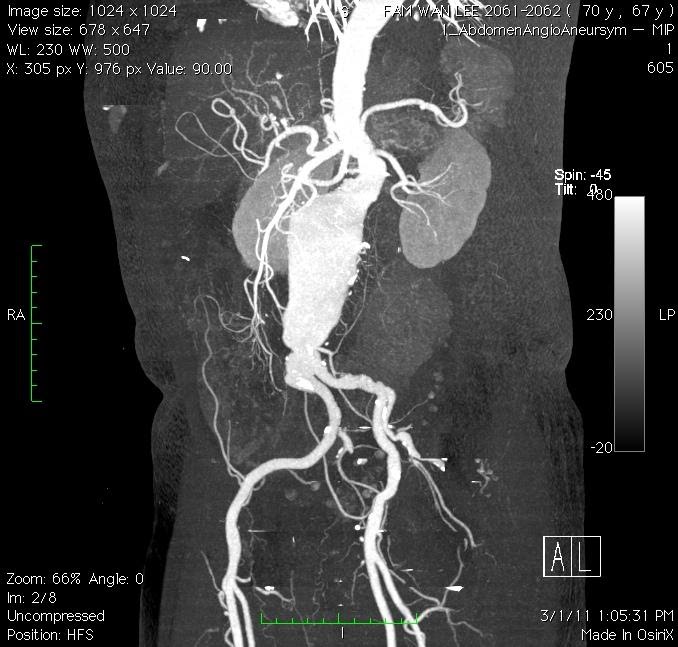

Modern diagnostic tools like ultrasonography (Figure 1) and computed tomography (CT) scan (Figure 2) makes the diagnosis much easier. The reported prevalence is around 4-8% in male and 1-2% in female after 70 year old. With ages beyond 80, the male to female ratio almost became 1:1.

Figure 2. CT scan delineates the anatomy of AAA